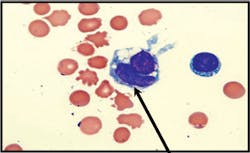

Image 3Papanicolaou-stained preparation showing numerous LE cells with

multilobed nuclei and a hematoxylin body. The LE cells on Papanicolaou-stained

preparations are smaller and show less nuclear compression of the

neutrophilic phagocyte by the hematoxylin body in comparison to the

appearance on Wright-Giemsa.

This case demonstrates that the cytologic examination of pleural fluid is

important as a diagnostic study. The finding of the single LE cell was

helpful in establishing the previously unsuspected diagnosis of lupus

pleuritis, so that beneficial treatment could be initiated. In the past, a

intensive and insensitive LE preparation, but LE cells may still be

encountered in preparations for fluidcell counts or cytopathology

examination (see Image 3). Nevertheless, recognition and reporting of these

cells, when found incidentally, can still be valuable as illustrated in this

case of laboratory microscopic lights and radiographic imaging shadows.